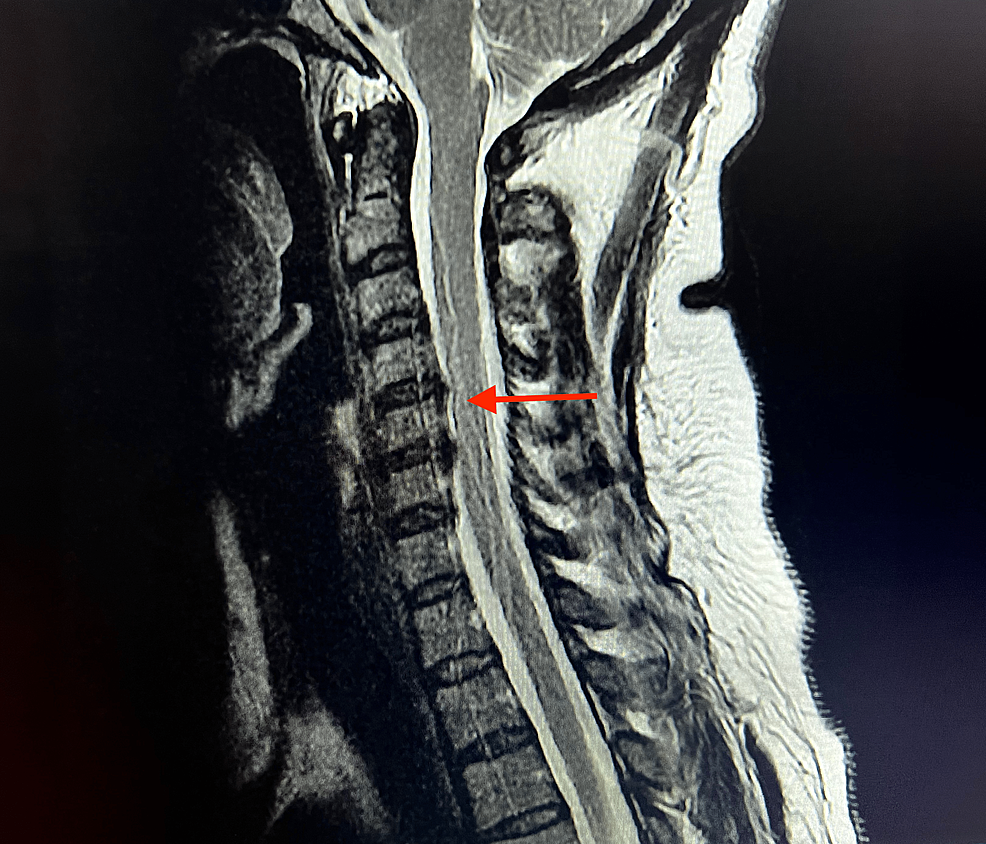

From www.researchgate.net

MRI cervical spine study at time of admission in ICU of our institute What Is A Cervical Mri Without Contrast Mri with and without contrast is done because it allows better detection and diagnosis of abnormalities. A cervical mri (magnetic resonance imaging) scan uses energy from strong magnets to create pictures of the part of the spine that runs. A cervical mri scan is a medical imaging test that generates pictures of the cervical, or neck region. A cervical mri. What Is A Cervical Mri Without Contrast.